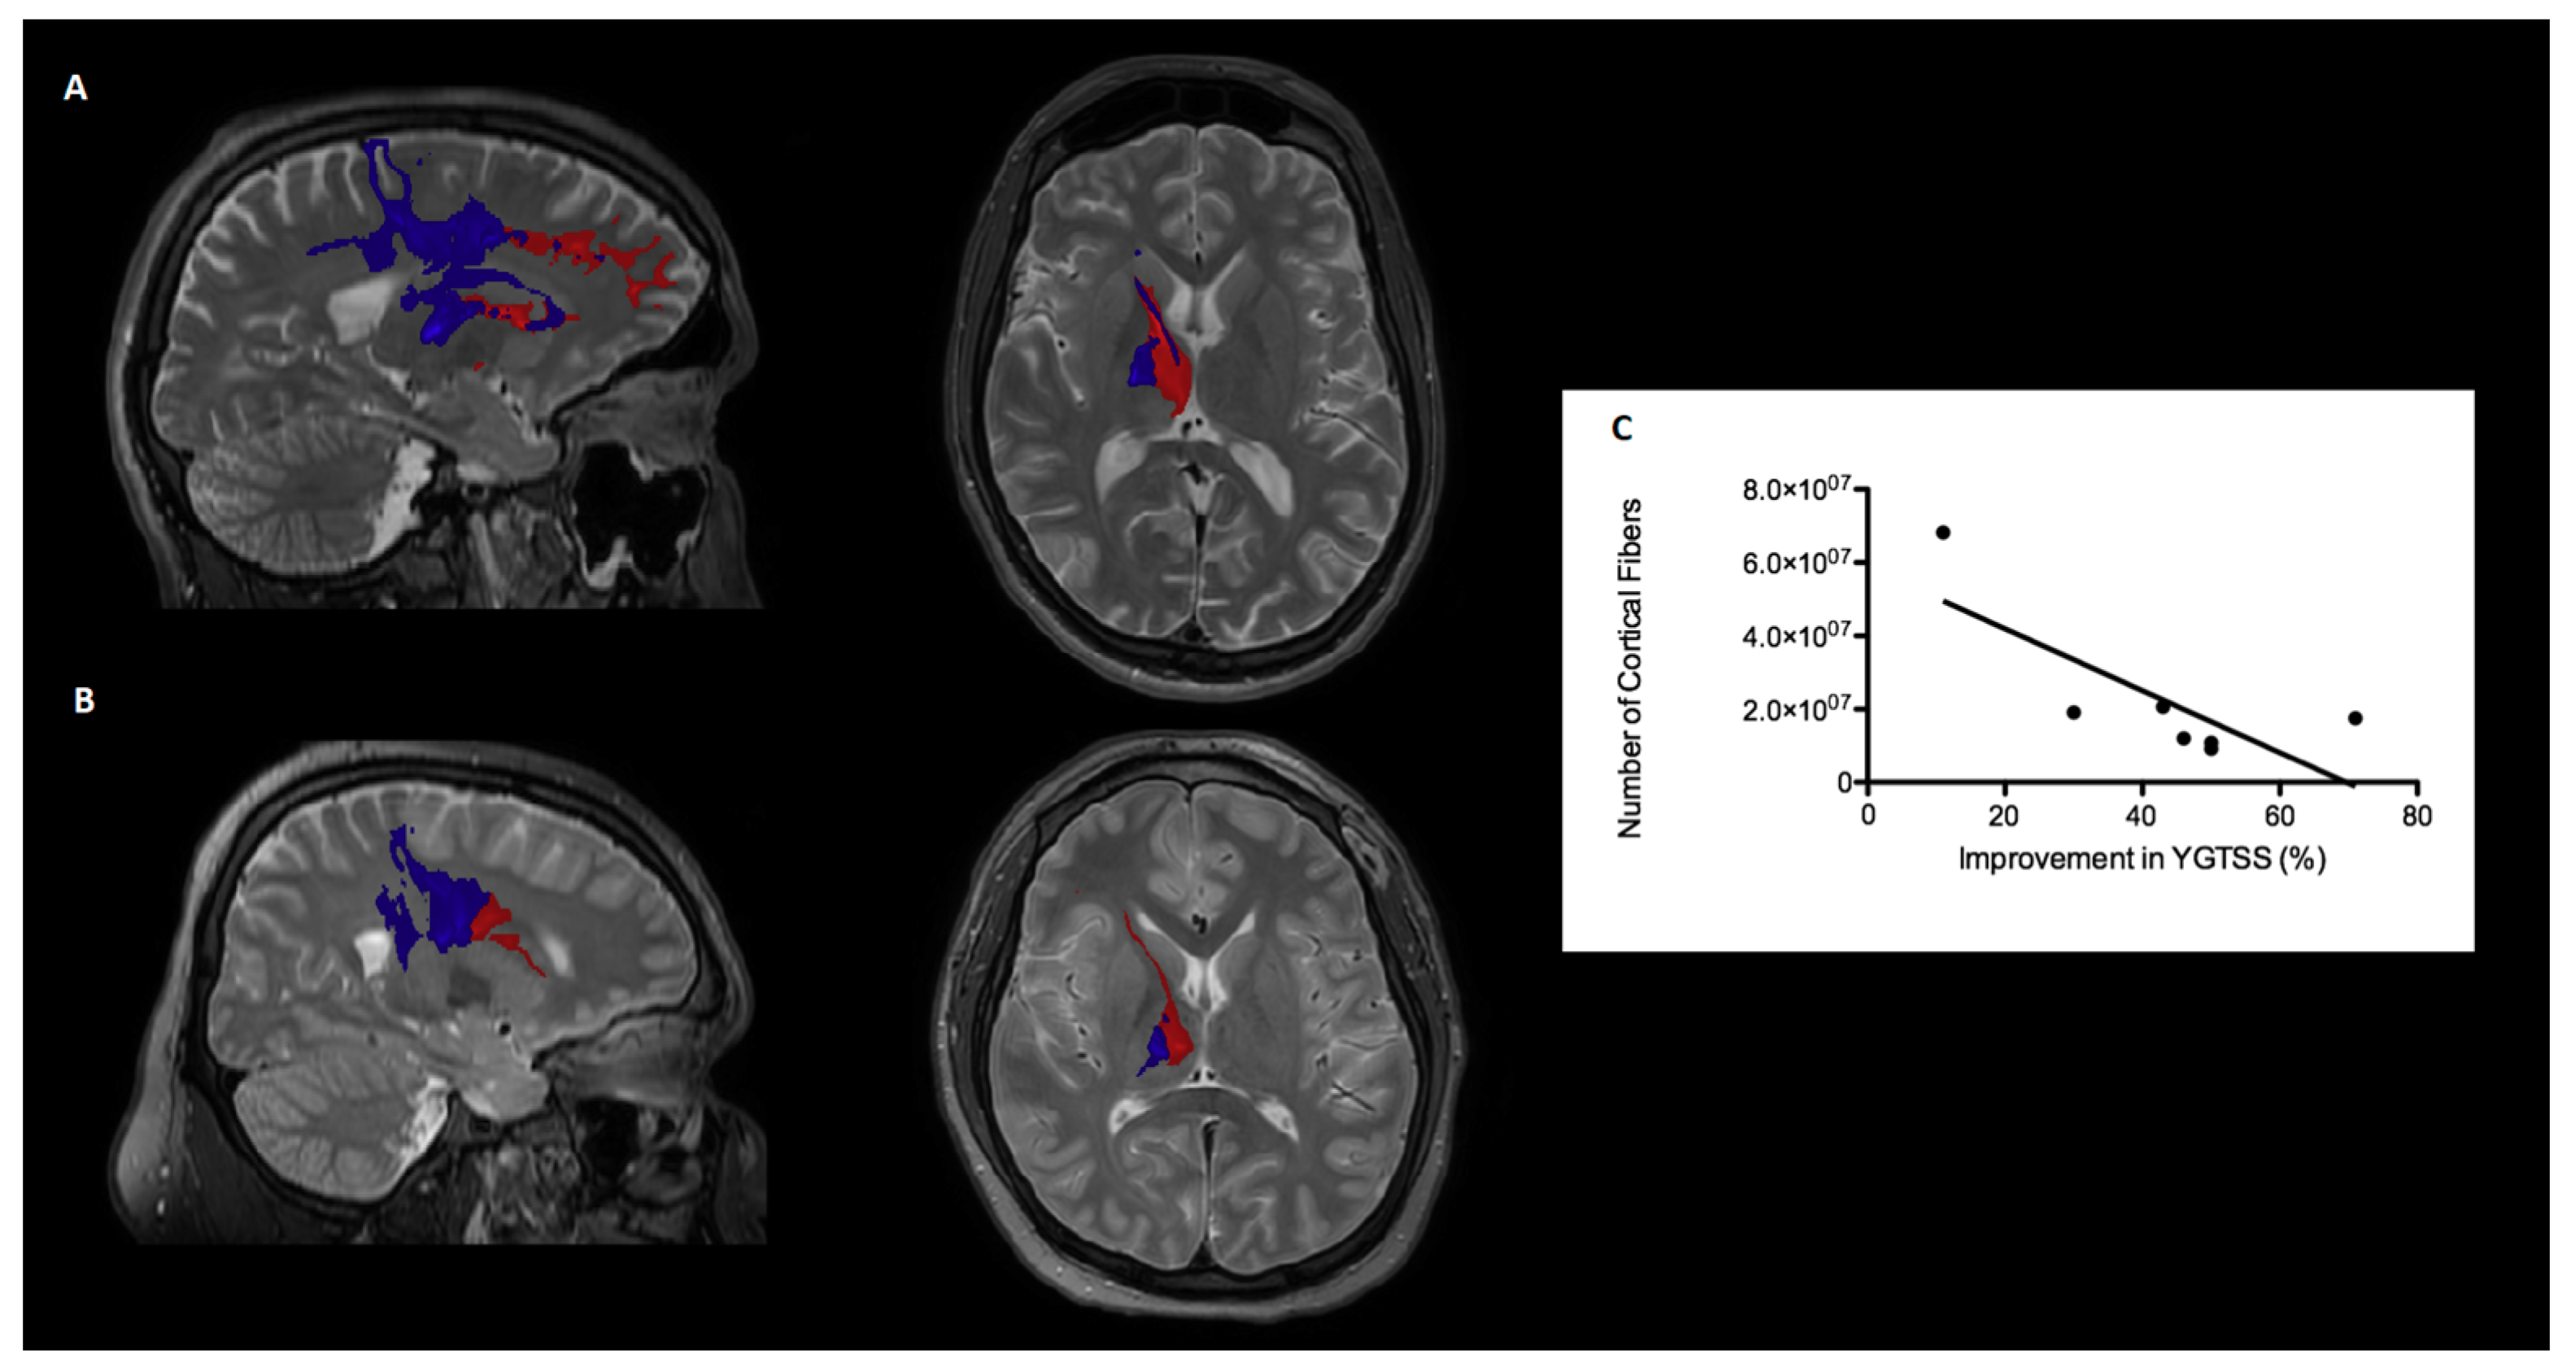

3.2.1. Generation of Fiber Tracts and Cortical Projections

3.2.3. Density of Fibers in the Motor Cortex